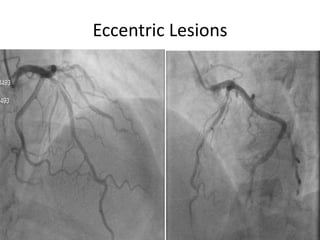

Limitations of Angiographic

assessment

• Inadequate vessel opacification. Guide not

properly engaged, streaming effect.

• Eccentric and calcified lesions – inaccurate

• Superimposition of branches.

• Microchannel recanalization :- difficult to

differentiate CTO with well developed bridging

collaterals or tightly stenotic lesion.

Assessment of coronary artery

stenosis by angiogram

• Luminogram

• Purely anatomical

• Inter and intra observer variability

• Oculostenotic reflex

Eccentric Lesions